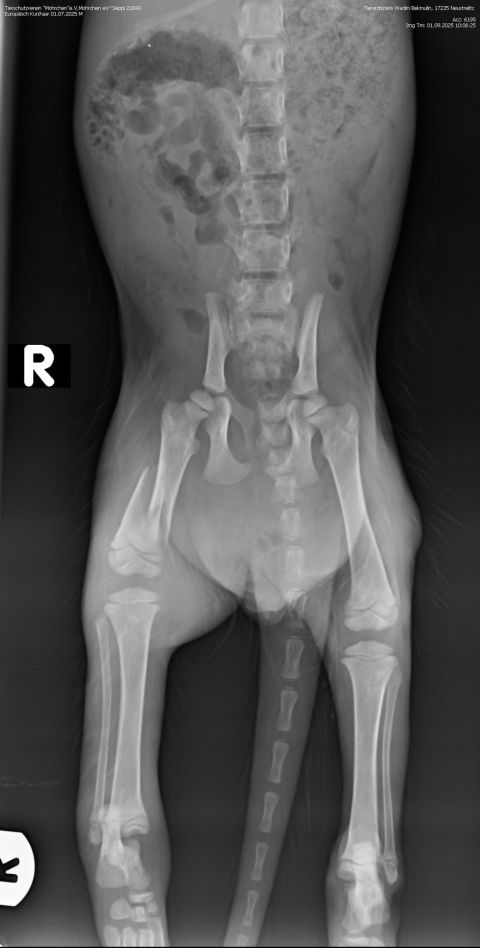

Ganz ohne Operation wird es aber dennoch nicht gehen: Auf dem Röntgenbild wurde festgestellt, dass Seppi einen Schwanzabriss erlitten hat. Sein Schwanz muss daher amputiert werden. Daran führt leider kein Weg vorbei.

Nun kann es schnell gehen - und das ist auch nötig: Denn die Röntgenbilder zeigen,dass der Oberschenkel stark verschoben ist und ihm große Schmerzen bereitet.

Beim Tierarzt haben wir erfahren, dass Seppi einen schweren Oberschenkelbruch erlitten hat. Damit er schmerzfrei laufen kann und keine bleibenden Schäden entstehen,

muss der kleine Kerl dringend operiert werden. Die Kosten werden sich voraussichtlich auf ca. 1.300 Euro belaufen. Eine Summe, die wir nicht alleine stemmen können. Deshalb bitten wir um Hilfe. Jede Spende, egal in welcher Höhe, zählt. Unser Ziel ist es, dass Seppi eine gute Chance auf eine gesundes Leben erhält.